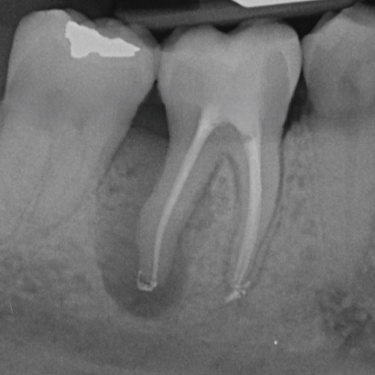

Fractura Radicular Vertical

Una fractura radicular vertical es una fisura que se extiende a lo largo de la raíz del diente, a menudo causada por un trauma o una presión excesiva.

Los pacientes suelen sentir dolor al morder y pueden notar hinchazón.

La fractura generalmente requiere la extracción del diente, ya que es difícil de reparar. Es crucial tratarla rápidamente para evitar infecciones.